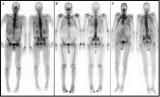

JNM发布了神经内分泌肿瘤SSTR PET成像的程序标准/实践指南

核医学和分子影像学会(SNMMI)和欧洲核医学协会(EANM)发布了一项新的神经内分泌肿瘤(NETs)患者生长抑素受体(SSTR) PET成像的新程序标准/实践指南。该标准/指南发表在《核医学杂志》(JNM)二月刊上,旨在帮助医生为NETs患者推荐、执行、解释和报告SSTR PET成像研究的结果。